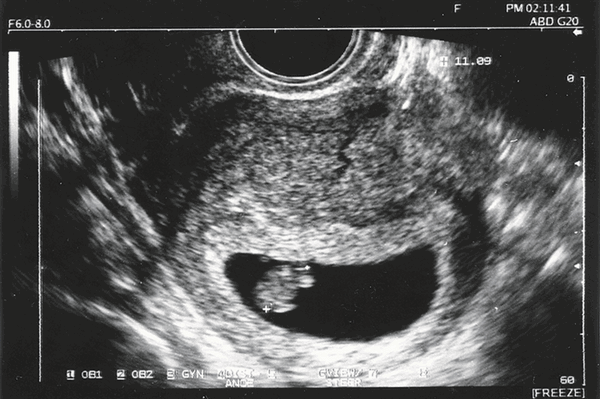

Фото УЗИ ребенка на 12 неделе беременности

Это очень важный период, поскольку гинеколог направляет женщину на первый скрининг. Он включает УЗИ и биохимический анализ венозной крови на гормоны. Ультразвуковое исследование в это время очень информативно и позволяет определить ряд врожденных патологий.

Визуально на фото видны такие особенности плода:

- хорошо просматриваются глаза (они обычно закрыты), нос малыша и другие черты лица;

- ребенок может открывать рот и глотать околоплодные воды;

- размеры плода все еще непропорциональны, но все части тела сформированы;

- в области половых органов происходит гипотрофия мошонки у мальчиков или гипертрофия половых губ у девочек (по этим признакам можно определить пол);

- движения плода хаотичные.

Скрининг на 12 неделе позволяет определить ряд патологий внутриутробного развития. Для этого аппарат УЗИ проводит ряд автоматизированных замеров. На основе этих измерений производят оценку формирования плода.

В этот период обязательно определяют такие параметры:

- длина плода;

- длина бедра;

- окружность живота;

- обхват головы;

- копчико-теменной размер (КТР) - длина от темечка до копчика;

- бипариетальный размер (БПР) - размер от одного виска до другого;

- толщина воротникового пространства;

- объем грудной клетки;

- вес плода (рассчитывается исходя из замеров).

Сопоставить эти данные и выявить патологию может только врач. Если специалист подозревает врожденное заболевание, назначают дополнительный хромосомный анализ.